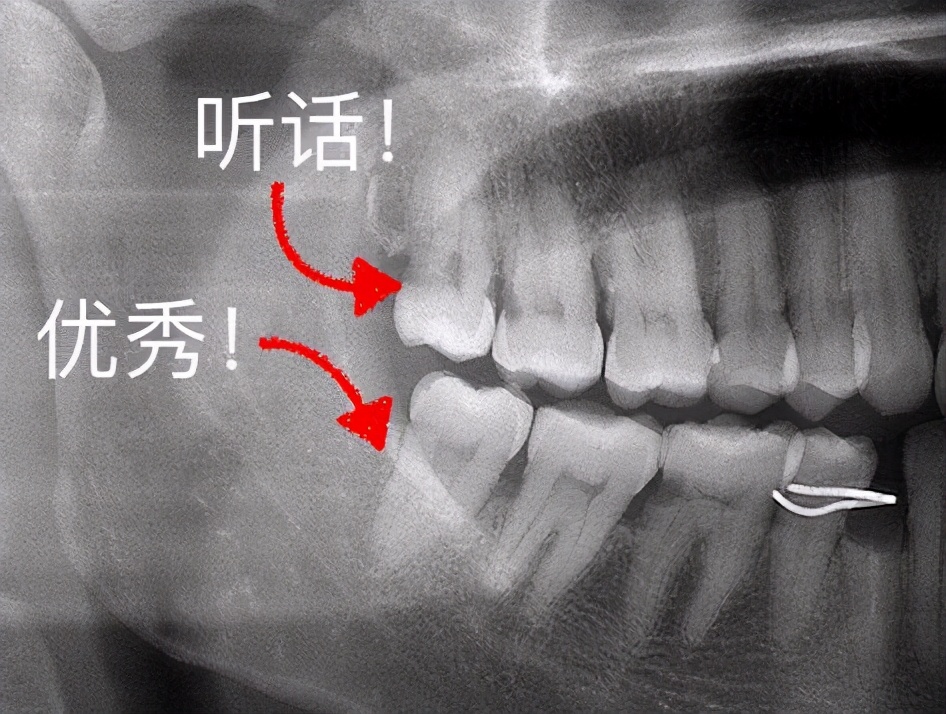

最后,不知道自己是否有长智齿的小伙伴,别再照镜子看了!有没有长智齿,拍个牙片一路了然。像埋伏智齿是照镜子无法看到的,只能通过拍牙片才能发现。#拔牙#